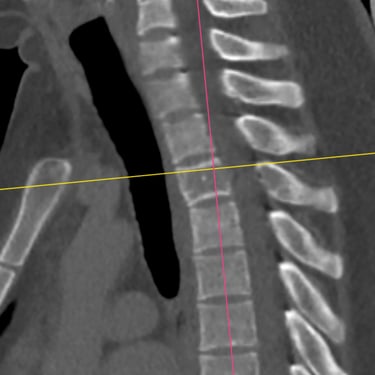

Tumor vertebral dorsal hemorrágico: descompresión medular, biopsia y artrodesis dorsal

El tumor vertebral dorsal puede ocasionar compresión de la médula espinal, dolor intenso y alteraciones neurológicas progresivas. En algunos casos, estos tumores presentan componente hemorrágico que incrementa la presión sobre las estructuras nerviosas. El tratamiento quirúrgico puede incluir descompresión medular para liberar la médula espinal, toma de biopsia para establecer el diagnóstico histopatológico y artrodesis dorsal con instrumentación para estabilizar la columna vertebral. Este abordaje permite reducir el riesgo de daño neurológico, aliviar los síntomas y mantener la estabilidad vertebral. La cirugía se realiza con técnicas especializadas que buscan preservar la función neurológica y mejorar la calidad de vida del paciente.